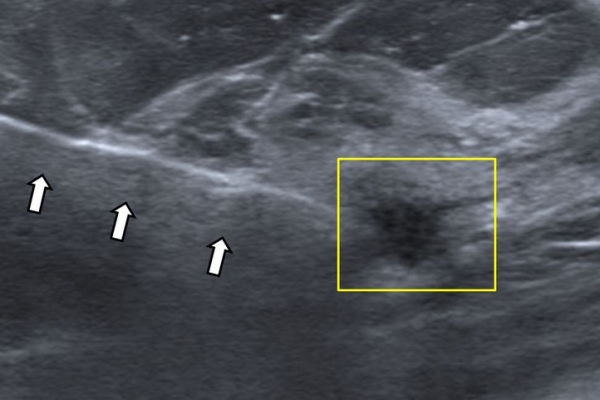

- Υπερηχογραφικά καθοδηγούμενη βιοψία μαστού - core biopsy

Εχει αντικαταστήσει την FNA στις συμπαγείς βλάβες του μαστού, γιατί η ποσότητα του ιστού που συλλέγεται είναι μεγαλύτερη και το αποτέλεσμα πιο αξιόπιστο.